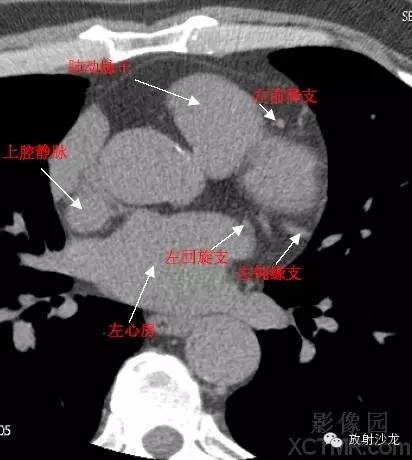

SVC –Superior Vena Cava上腔静脉

LMA -Left Main Artery冠状动脉左主干

LAD -Left Anterior Descending Artery左前降支

LCX -Left Circumflex Artery左回旋支

LMB -Left Obtuse Marginal Branch 左边缘支(钝缘支)